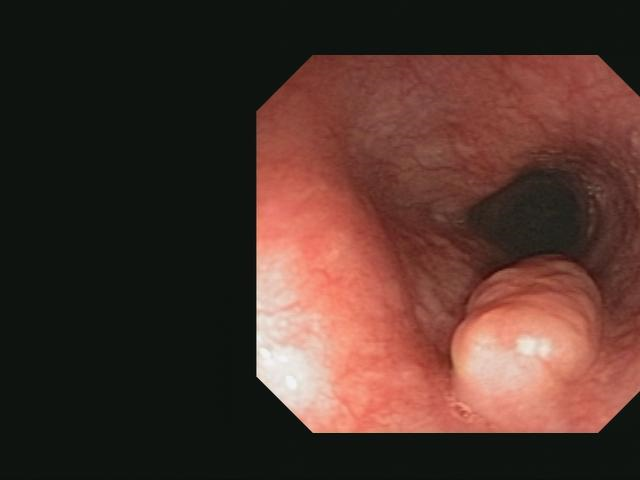

Nonepithelial Esophageal Tumors: Leiomyomas and GI Stromal Tumors

- Classification and diagnosis of GISTs changed substantially over the past decades.

- Immunohistochemical expression of CD117 is one of the most sensitive markers for diagnosing GISTs.

- Another important advance is development of minimal invasive surgical techniques.

- Most of these tumors can be surgically removed by either a VATS or a laparoscopic approach.